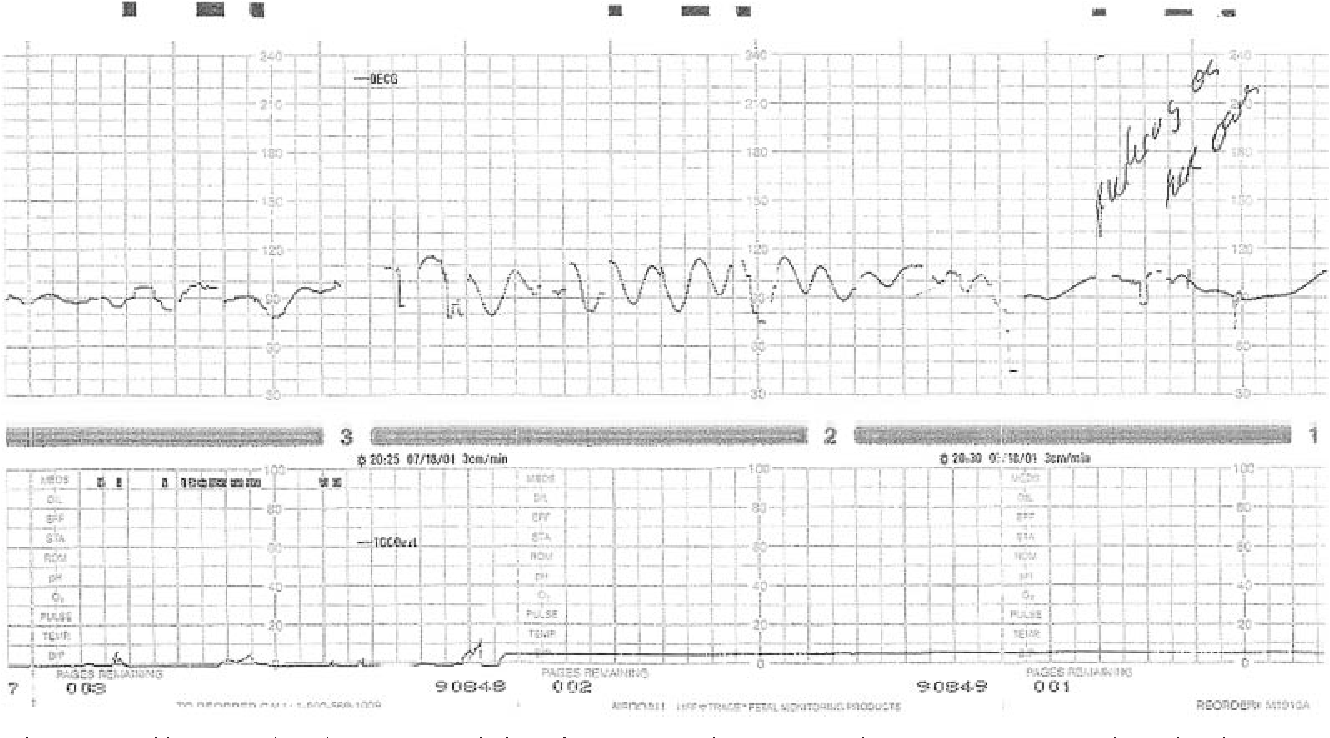

These patterns are characterized by a smooth, regular, and symmetrical waveform on the fetal heart rate monitor. They are different from the typical heart rate patterns seen during labor and delivery and may indicate certain underlying conditions.

Sinusoidal fetal heart rate patterns can be a cause for concern as they may be associated with fetal distress. It is important for healthcare providers to monitor these patterns closely and take appropriate action to ensure the well-being of both the mother and the baby.

There are various factors that can contribute to the development of sinusoidal fetal heart rate patterns, including fetal anemia, maternal bleeding, and certain medications. It is essential for healthcare providers to identify the underlying cause of these patterns and address it promptly.

If sinusoidal fetal heart rate patterns are detected during labor and delivery, healthcare providers may recommend additional tests and interventions to assess the baby’s well-being and ensure a safe delivery. Close monitoring and timely intervention can help prevent complications and improve outcomes for both the mother and the baby.

Figure 2 From Title Sinusoidal Heart Rate Pattern Reappraisal Of Its Definition And Clinical Significance Semantic Scholar